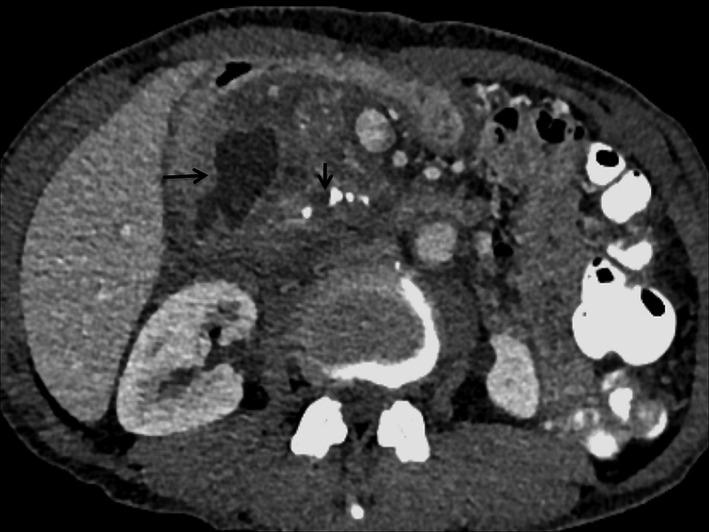

Pancreatitis is one of the important medical conditions. Gastrointestinal (GI) complications of pancreatitis are important and lead to significant morbidity and mortality. Diagnosis of these complications is difficult and may require a strong clinical suspicion coupled with various imaging features. This review provides an extensive update of the whole spectrum of GI complication of pancreatitis, both acute and chronic, from inflammation, ischemia, and necrosis to obstruction, perforation, and GI fistulae. The focus is on the clinical and imaging features of this less commonly described aspect of pancreatitis.

胰腺炎是重要的医学病症之一。胰腺炎的胃肠道并发症很重要,会导致显著的发病率和死亡率。这些并发症的诊断困难,可能需要高度的临床怀疑以及各种影像学特征。本综述全面更新了胰腺炎胃肠道并发症的全貌,涵盖急性和慢性,从炎症、缺血和坏死到梗阻、穿孔及胃肠道瘘。重点在于胰腺炎这一较少被描述方面的临床和影像学特征。